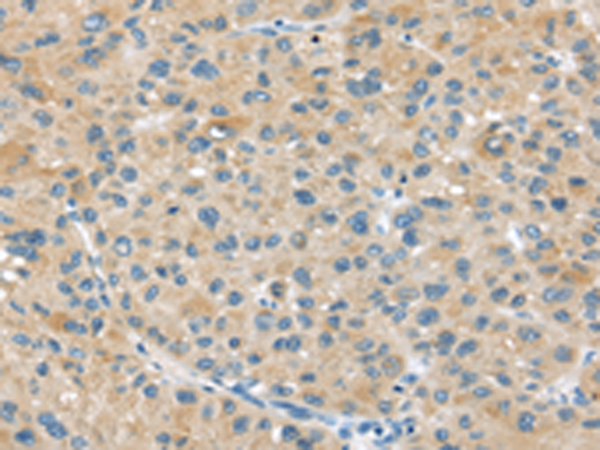

分类: 科研抗体货号: P11028别名: DJS; MRP2; cMRP; ABC30; CMOAT应用: IHC反应种属: Human